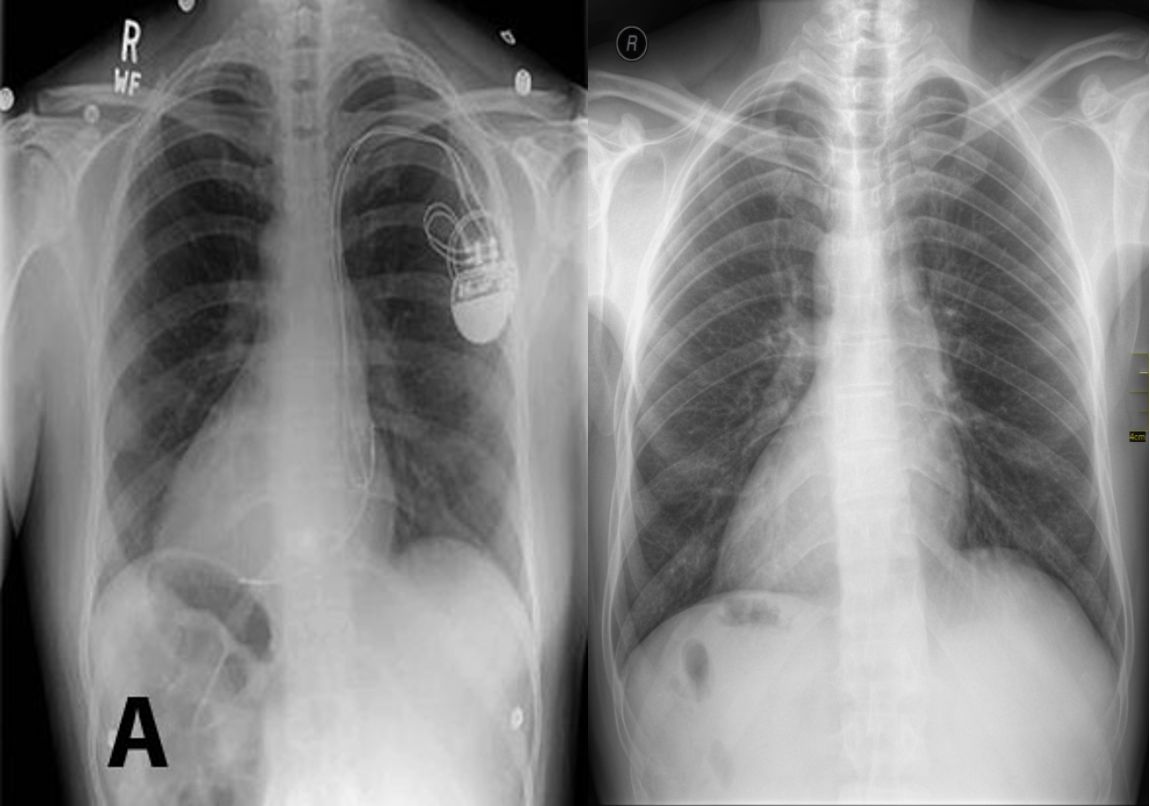

Dextrocardia with right sided aortic arch